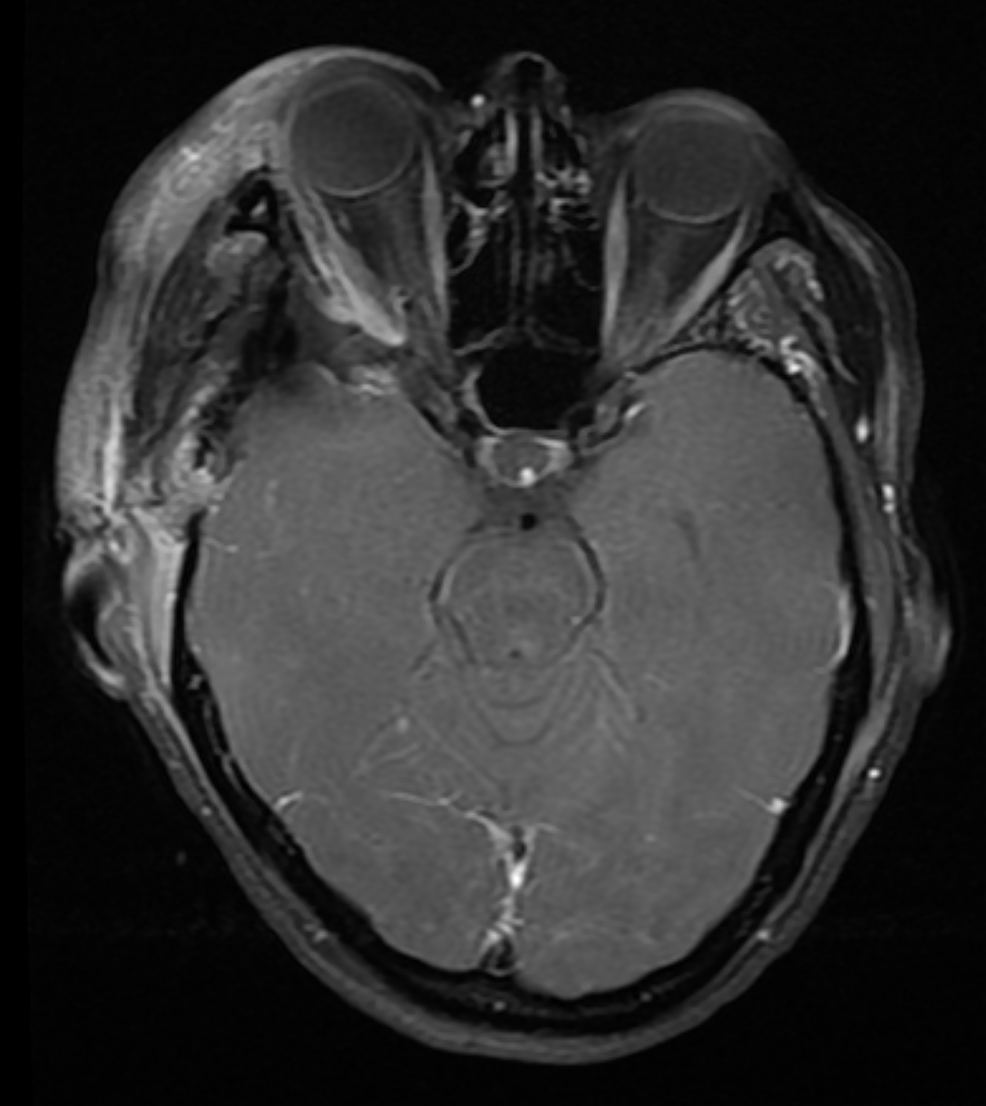

Brain MRI showing titanium cranioplasty without signs of relapse Titanium Plate In Skull Mri This study reviews the current literature on mri safety with orthopedic implants. This study assesses and quantifies impairment of postoperative magnetic resonance imaging (mri) at 7 tesla (t) after implantation of. A titanium plate for cranioplasty is considered to be safe for implantation in humans, and it is one of the most widely used biomaterials. As polymers and ceramics are. Titanium Plate In Skull Mri.